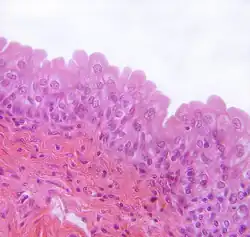

Buňky vlhkých vrstevnatých krycích epitelů

- povrchová epiteliální buňka vrstevnatých dlaždicových epitelů v rohovce, na jazyku, v ústní dutině, jícnu, análním kanálu, distálním konci močové trubice a ve vagině

- bazální buňka těchto epitelů (vlastně kmenová buňka)